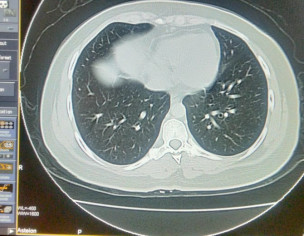

Asking for Sister, Female, 33 years old, Isl

Plz describe it. Film of hrct of corona patient

plz contact radiologist

Send full films, its incomplete